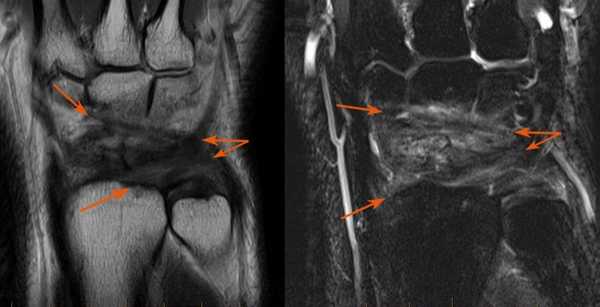

МРТ кисти. Корональная Т1-взвешенная и Т2-взвешенная МРТ. Трабекулярный перелом лучевой кости без смещения.

МРТ кисти. Корональные Т1- и Т2-взвешенные МРТ. Повреждение задней группы связок.

Очень сложны в диагностике переломы ладьевидной кости - они часто пропускаются на рентгенограммах. Осложнением такого перелома может стать асептический ее некроз. На Т2-взвешенных МРТ при переломах виден отек костного мозга, обычно частично охватывающий кость.